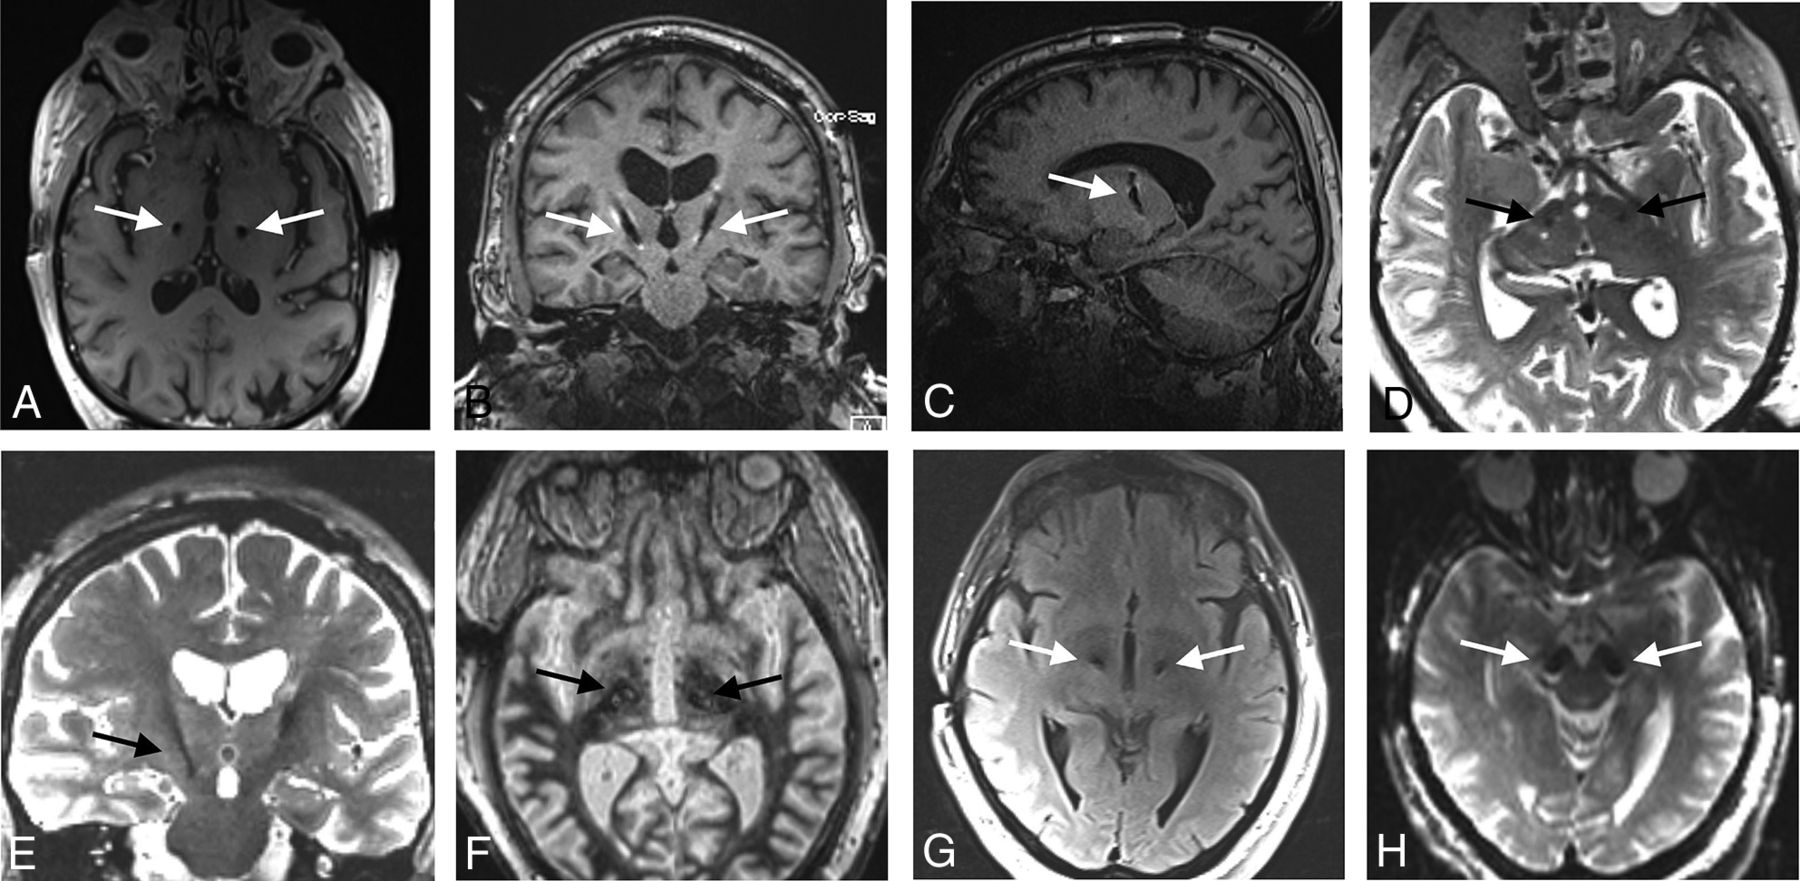

The procedure for iMRI-DBS placement has been described in detail elsewhere.8 In brief, after the induction of general anesthesia, the patient’s head is fixed to the MRI gantry with a custom 4-pin head holder (MRI Interventions). After sterile preparation and draping, the skull entry site is marked through the skin, the scalp is opened, and a skull-mounted miniframe (SmartFrame, MRI Interventions) is rigidly affixed using bone screws. MR imaging scans are obtained according to manufacturer specifications, the target is selected by using intraoperative images, and the miniframe is iteratively adjusted until the cannula is aimed at target with less than 1-mm projected radial error. A ceramic stylet and peel-away sheath are then placed to target, and the actual error is measured. If stylet placement is acceptable (as determined by the surgeon, with 1.5-mm radial error being the usual cutoff), the stylet is replaced by the DBS electrode, and the peel-away sheath is removed. Postplacement images may be performed immediately after electrode placement, with the proximal ends of the electrodes extended within the bore of the scanner (“externalized”), after the electrodes have been secured with silicone boots and coiled under the closed scalp incision (“internalized”), or both. Examples of iMRI are shown in Fig 1.

Sample iMRI before and after DBS placement. The left side of the figure shows intraoperative 3D T1 FLASH images of ceramic stylet placement in the left Vim (upper image, coronal; lower image, sagittal). The right side of the figure shows bilateral DBS electrode placement in the same patient. See “Surgical Procedure” in the Methods section for details.